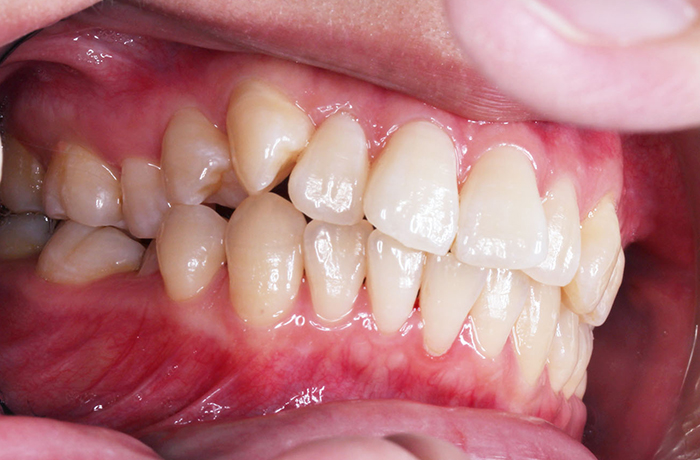

K様

治療前

before

治療後

after

年齢 27歳

性別 女性

治療名称 マウスピース型カスタムメイド矯正歯科装置(インビザライン)・コンプリヘンシブパッケージ(フルパッケージ)

総額治療費用 770,000円(税込10%) 金額備考 精密検査料・診断料 33,000円(税込10%)

治療期間 1年11か月 通院頻度など 40日ごと

1枚につき10日装着を指示しました。

患者の症状 上顎前歯の前突、八重歯

治療方法 上下左右の第一小臼歯抜歯で、マウスピース型カスタムメイド矯正歯科装置による矯正

治療結果 上顎前歯の前突、八重歯が改善されました。

歯並びをより良くするために追加でアライナーを発注しました。

リスク/副作用 決められた時間装着する必要があります。